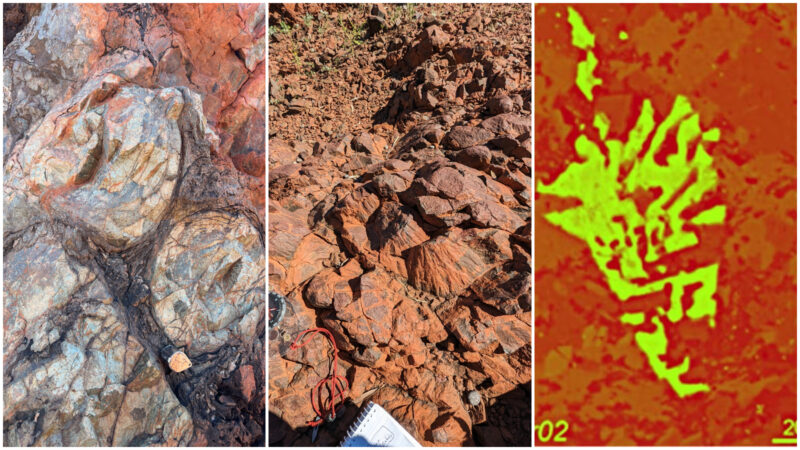

КТ-сканирование черепа женщины выявило травму головы, разрушившую ее правый височно-нижнечелюстной сустав (ВНЧС). Травма должна была лишить женщину возможности нормально говорить и есть. Учитывая, что пазырыкцы постоянно ездили верхом, женщина могла получить травму при падении с лошади на галопе, согласно заявлению.

Хотя травма женщины не была чем-то необычным, уникальное лечение повреждения ее костей и связок удивило исследователей. Они обнаружили тонкие каналы, просверленные в двух костях, образующих правый ВНЧС женщины, а также конский волос или сухожилие животного в каналах, скрепляющих сустав.

«Этот примитивный протез удерживал суставные поверхности вместе и позволял пациентке двигать челюстью», — сказал Летягин. «Сустав функционировал, но она все еще не могла жевать пищу на травмированной стороне, вероятно, из-за сильной боли».

Несколько аспектов черепа женщины показали, что она прожила несколько месяцев — или даже лет — после операции. Новая костная ткань образовалась вокруг каналов в ее правом ВНЧС, а зубы на левой стороне челюсти были стерты и сколоты, что позволяет предположить, что она компенсировала травму правой стороны, жуя исключительно левой.